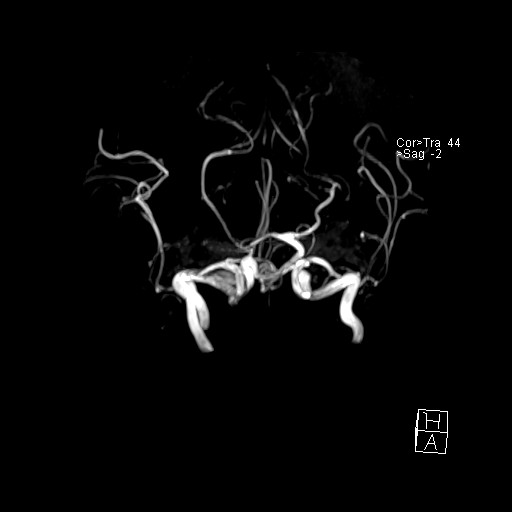

- VILLANUEVA, WILLIAM A. MR HEAD

- VILLANUEVA, WILLIAM A. MR HEAD

- VILLANUEVA, WILLIAM A. MR HEAD

- VILLANUEVA, WILLIAM A. MR HEAD

- VILLANUEVA, WILLIAM A. MR HEAD

- VILLANUEVA, WILLIAM A. MR HEAD

- VILLANUEVA, WILLIAM A. MR HEAD

- VILLANUEVA, WILLIAM A. MR HEAD

- VILLANUEVA, WILLIAM A. MR HEAD

- VILLANUEVA, WILLIAM A. MR HEAD

- VILLANUEVA, WILLIAM A. MR HEAD

- VILLANUEVA, WILLIAM A. MR HEAD

- VILLANUEVA, WILLIAM A. MR HEAD